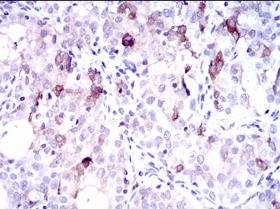

SLC27A5 Mouse Monoclonal antibody[9C461]

IHC    1/200 - 1/1000